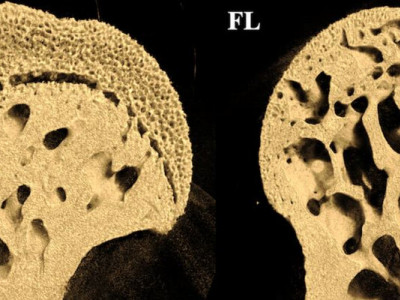

Втрата кісткової маси в космосі: Дослідження мишей NASA в мікрогравітації розкриває несподівані висновки

Нове дослідження NASA на мишах на борту Міжнародної космічної станції розкриває, чому знижується щільність кісток у мікрогравітації. Дослідження підкреслює значний вплив на кістки, що несуть ваг